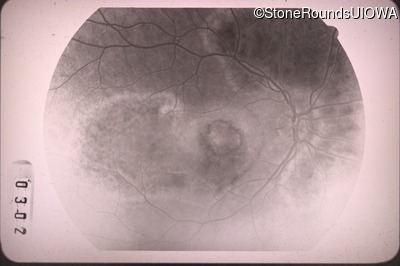

Fluorescein Angiography - Right - 20/100 -1

Exemplar

Fluorescein Angiography - Left - 20/40 -1